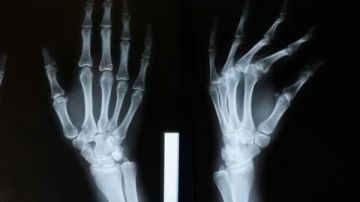

في خطوة وصفت بأنها نقلة نوعية في عالم الطب، أعلن فريق بحثي صيني عن ابتكار طبي جديد قد يغيّر مستقبل جراحة العظام. الابتكار يتمثل في 'غراء عظمي' قادر على معالجة الكسور وتثبيت الشظايا العظمية خلال ثلاث دقائق فقط، وهو إنجاز قد يختصر الوقت والجهد ويقلل من المضاعفات الجراحية.

يتميز الغراء بقدرته على التثبيت السريع والدقيق في أقل من 180 ثانية، ما يجعله بديلاً محتملاً عن الطرق التقليدية التي تتطلب وقتاً أطول لزراعة الصفائح الفولاذية والمسامير. والأهم من ذلك أنه يُمتص طبيعياً من الجسم مع مرور الوقت، مما يلغي الحاجة إلى إجراء عملية جراحية لاحقة لإزالة المواد المعدنية.

أظهرت التجارب المعملية أن Bone-02 يتمتع بقوة ربط تفوق 400 رطل، إضافة إلى قوة قص تبلغ نحو 0.5 ميغاباسكال، وقوة ضغط تقارب 10 ميغاباسكال. كما جُرّب الغراء على أكثر من 150 مريضاً، وجاءت النتائج مشجعة، حيث أثبت فاعليته وأمانه، فضلاً عن تقليل احتمالية حدوث التهابات أو مضاعفات بعد العملية.